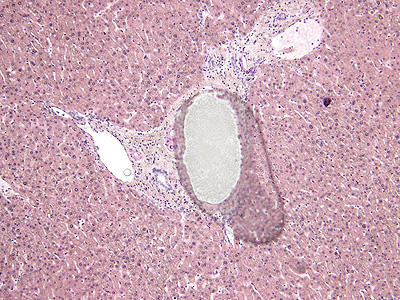

脱水が不完全のまま透徹封入した標本で、中央に水滴が認められる。

水滴の他、細胞質の染色性が低下を来す。